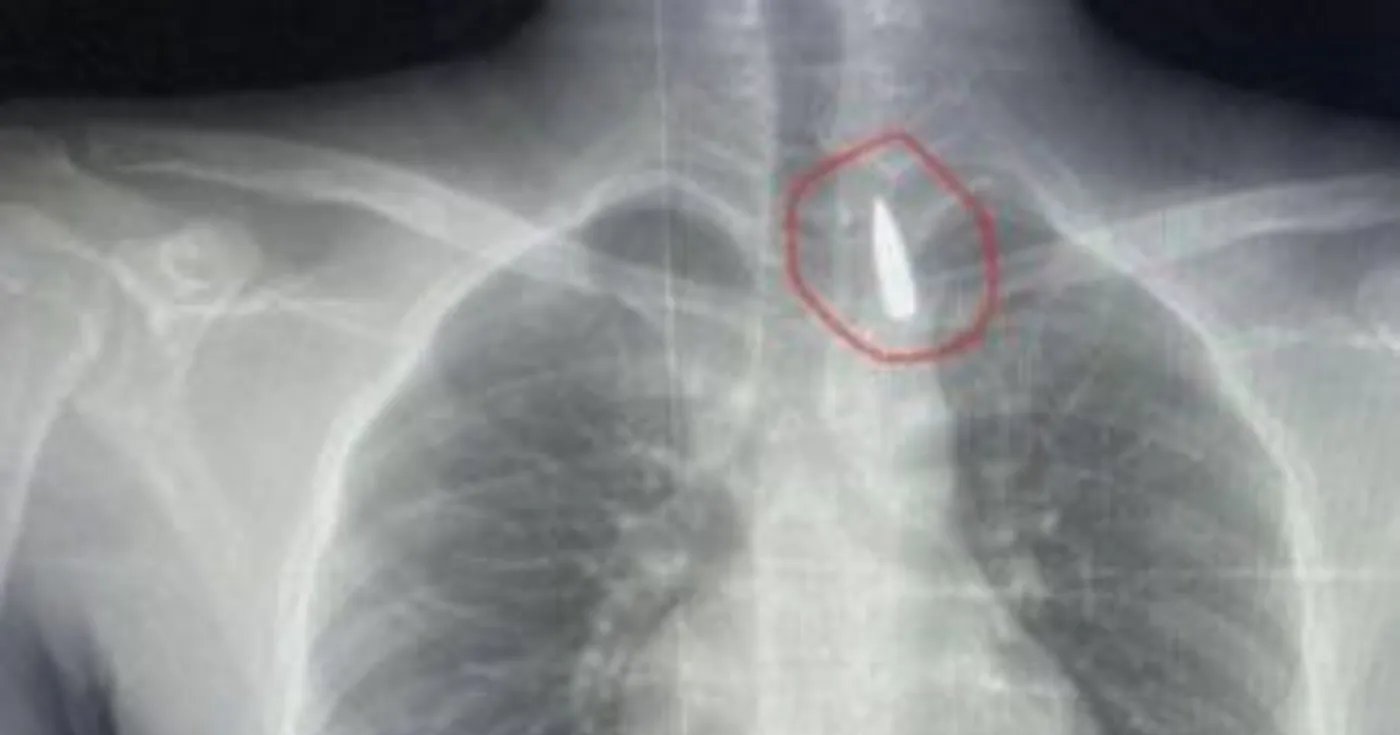

إنقاذ مصاب من غزة بعد استخراج مقذوف استقر في صدره

السوسنة - في إنجاز طبي استثنائي، نجح فريق طبي مصري من مستشفيات جامعة الإسكندرية في إنقاذ حياة مصاب فلسطيني من قطاع غزة، بعد إجراء عملية جراحية دقيقة لاستخراج مقذوف ناري استقر قرب الشريان الأورطي داخل تجويف القفص الصدري، في حالة وصفت بأنها بالغة الخطورة.

وأوضح الدكتور تامر عبد الله، عميد كلية الطب ورئيس مجلس إدارة المستشفيات الجامعية، أن العملية استغرقت عدة ساعات، وشارك فيها أطباء متخصصون في جراحة القلب والصدر والتخدير، وتم خلالها إزالة المقذوف بأمان، رغم قربه من أهم شرايين الجسم المسؤول عن تغذية الأعضاء الحيوية.

وأكد أن حالة المريض مستقرة حاليًا وتخضع لمتابعة دقيقة من الفريق الطبي، مشيرًا إلى أن هذا النجاح يعكس كفاءة الكوادر الطبية المصرية وقدرتها على التعامل مع أكثر الحالات تعقيدًا.

وفي تصريح خاص لموقع "سكاي نيوز عربية"، وصف المتحدث باسم وزارة الصحة المصرية، الدكتور حسام عبد الغفار، العملية بأنها إنجاز طبي نادر، يتطلب تنسيقًا عاليًا بين تخصصات متعددة، من الجراحة العامة إلى الأوعية الدموية والتخدير والأشعة والرعاية المركزة.

وأشار إلى أن هذا النجاح لم يكن وليد الصدفة، بل نتيجة لتدريب متقدم، واستخدام أحدث تقنيات التصوير ثلاثي الأبعاد، وغرف عمليات مجهزة بأنظمة الملاحة الجراحية، ما يعكس جاهزية النظام الصحي المصري لاستقبال الحالات الإنسانية العاجلة.